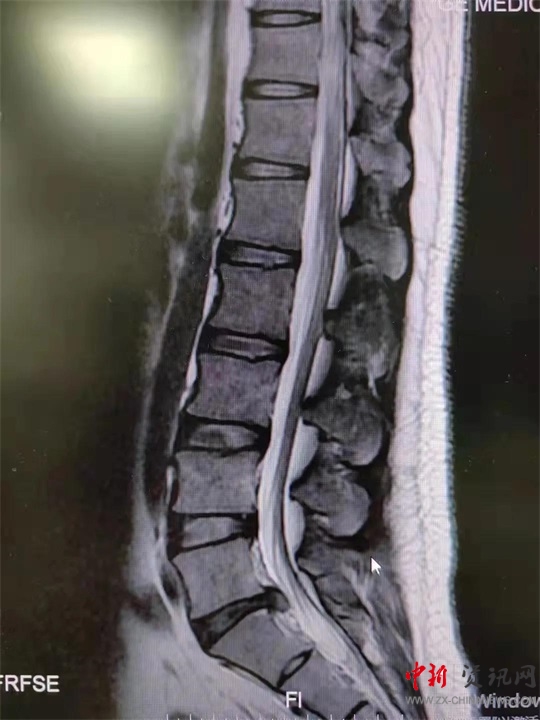

9月初,盧先生來到駐馬店市第一人民醫(yī)院就診。影像學(xué)檢查提示腰5骶1椎間盤突出;颊甙Y狀、體征與影像學(xué)表現(xiàn)相符,腰椎間盤突出癥診斷明確。結(jié)合患者情況,蔣學(xué)國主任團隊決定舍棄傳統(tǒng)手術(shù)方案,為患者實施UBE技術(shù)下腰椎間盤髓核摘除術(shù),這也是UBE技術(shù)在西院區(qū)的首次應(yīng)用。